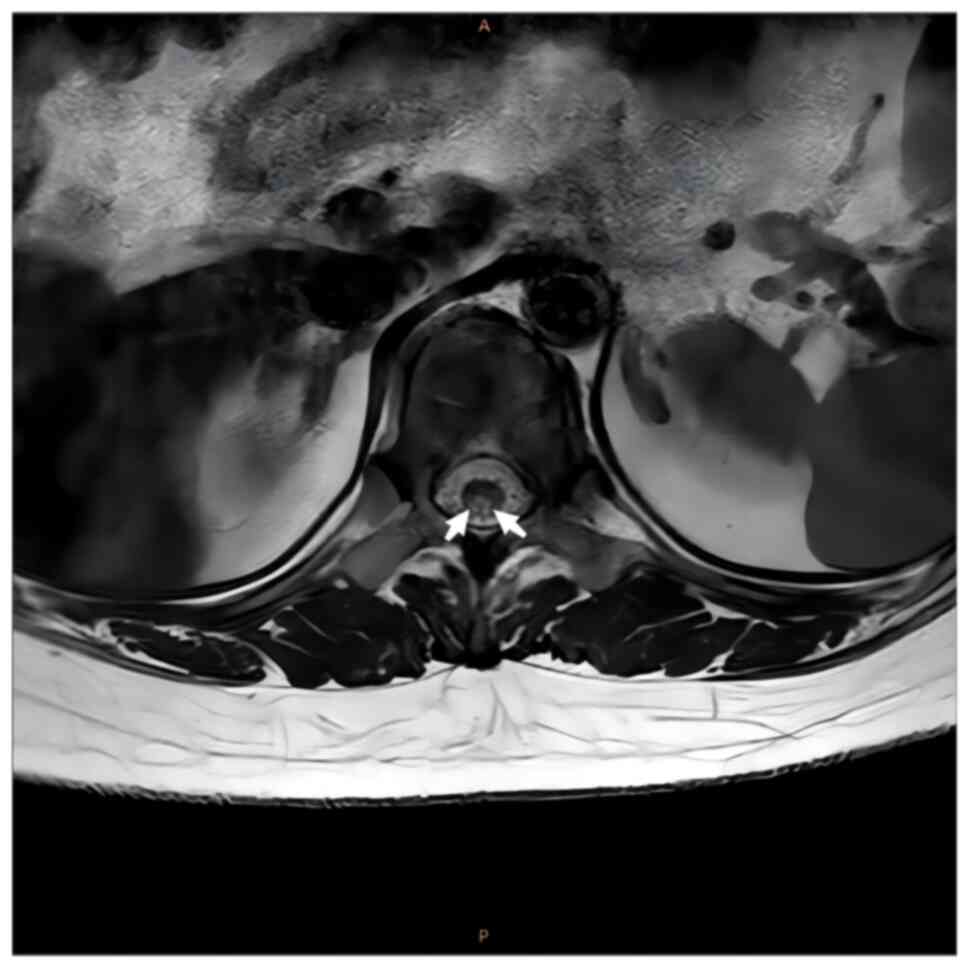

intramedullary signal with a high signal (Figs. 1 and 2). Axial images indicated that the

lesions mainly occupied the posterior portion of the spinal cord in

a ‘figure-eight sign’ (Figs. 3 and

signs were positive. SCD typically occurs in the cervical spinal

cord and the lesions usually cause a ‘figure-eight’ change in the

posterior cord.